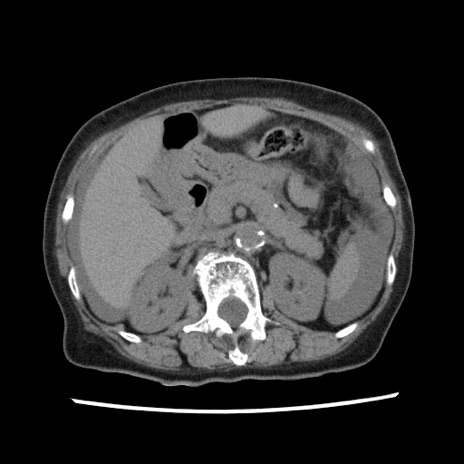

【症例】80歳代女性

【主訴】腹痛

【現病歴】8時間前から腹痛あり来院。

【既往歴】糖尿病、脂質異常症、子宮体癌にて子宮全摘術

【身体所見】意識清明・会話良好だが腹痛で苦悶様、全腹部にわたって反跳痛と圧痛あり

【データ】WBC 13600、CRP 0.14、LDH 224、CK 90